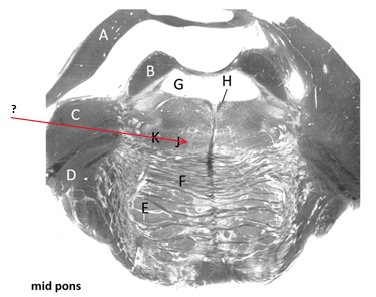

Name this and state its function.

Transverse pontine fibres.

Name this and state its pathway.

Fourth ventricle.

Third ventricle–>4th ventricle–> subarachnoid space.

Cerebellum.

Superior cerebellar peduncle.

Efferent pathway:

first —>= superior cerebellar peduncle

Middle cerebellar peduncle.

Medial longitudinal fasciculus.

Trigeminal nerve(root).

Pyramidal tracts.

Descending Pathway: Motor fibres, carrying information from Cortex—>brain and spine–> lower motor neurons.

Medial lemniscus.